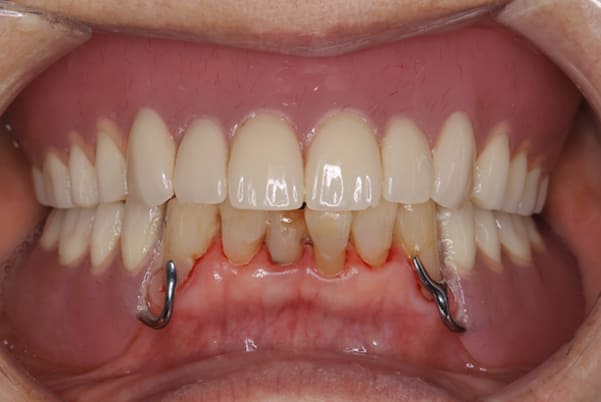

症例レポート[CASE.01]

義歯が合わず痛い、

見た目も気になる

- 性別・年齢

- 女性(40代)

- 主訴

- 下の義歯が合わず入れると痛みがある、見た目も気になるので外にはつけていかない

- 治療

- 下顎精密金属床部分入れ歯

- 治療期間

- 約2か月間

- 費用

- 55万円(税込)

入れ歯が沈み込むことを防止するストッパーがない入れ歯を装着されていたため、お食事により入れ歯が沈み込みお痛みがでている状態でした。

笑った際に、太いバネが左右に見えるため、あまり大きく笑うことを避けていらっしゃいました。

作製した入れ歯は、お食事の際に入れ歯の沈み込みを予防するため、適切なストッパーを付与することで、入れ歯は沈み込まなくなり、お痛みは消失しました。

右下のバネの位置は後ろに、左下のバネは見えづらい形態のバネを用いる設計とすることで笑った際にバネが見えないようになり、気にされることはなくなられました。

裏側の見えない部分は金属を用いることで、お食事の際の入れ歯の動き、沈み込みを抑えお痛みがでづらく、入れ歯の動きが抑制されることで、長期的に残りの歯に負担のかかりにくい設計としました。

治療前後の口元の比較

こちらは、口を少し開いた時の治療前と治療後の

口元です。

正面から見た時にクラスプが目立たないように、

歯ぐきになじむ素材にて入れ歯を製作し、痛くなく自然に馴染み快適に生活を送れるようになりました。